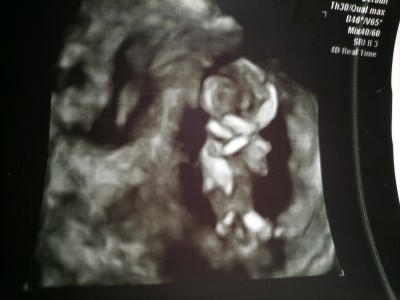

Çıkıntı var fotografta ben öyle görüyorum ama kordon o kız dedi doktor dediği gibi midir

Canım kız gibi yüzü aşağıda poposu yerde

Doktor da öyle dedi kız gibi gördüm ben ama hemen giysi alma dedi :)

Genital çizgisi de aşağıda

Canim cikinti boyle yandan onden gorulmez, bebegin alt bacak arasini denk getirip bakiyor doktor. Bu resimde gordugun hersey olabilir yani ultrason resmi sonucta normal fotograf degil yaniltici olur

Evet yuzde 70 diyolar bu haftalarda ama buyuk ihtimalle kizdir rabbim saglikla gelmeyi nasip etsin:)

Kac haftalik canin bana 12.haftda bir cikinti var erkek gibi  ama kordonuda olabilir bir sonraki kontrolde emin olalim dedi  ama  erkekmiş

12+6 dayım canım benim 11+6 da yken de kız gibi görünüyordu